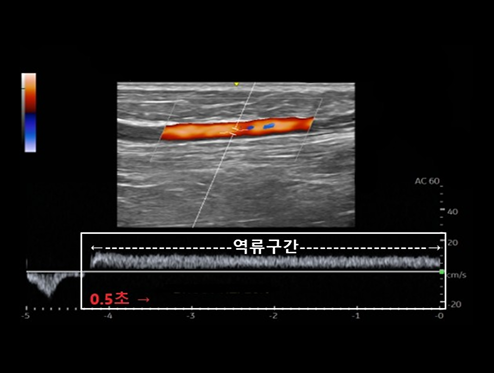

하지정맥류 진단은 혈액의 역류 진단은 육안으로는 다 알 수 없습니다.

혈관 초음파를 통해 발병 부위를 면밀히 관찰해야 합니다.

역류 0.5초 이상 역류 시 진단

도플러 초음파 검사라는 혈관 초음파 검사를 통해 고장난 판막의 위치와 역류 시간을 정확하게 파악할수 있는 검사입니다. |